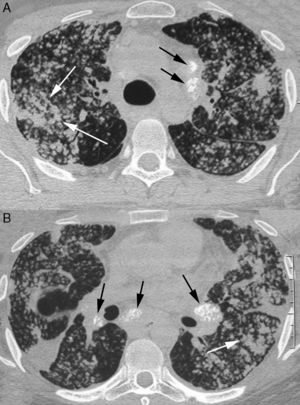

Los hallazgos de silicoproteinosis mediante TAC de alta resolución consisten en espacios de aire bilaterales que se manifiestan como consolidación, opacidades en vidrio esmerilado y nódulos centrilobulares. Se suele observar calificación puntiforme superpuesta en zonas de consolidación y ganglios linfáticos calcificados3,4 (fig. 1).

Varón de 29 años con silicoproteinosis. El paciente trabajaba como pulidor con arena en la industria naval, con un historial de exposición al sílice de 2,8 años. El TAC de los lóbulos superiores (A) e inferiores (B) muestra numerosos nódulos de espacios de aire bilaterales, algunos confluentes (flechas blancas) con zonas de consolidación en ambos pulmones. Se evidencian ganglios linfáticos mediastínicos e hiliares calcificados (flechas negras).